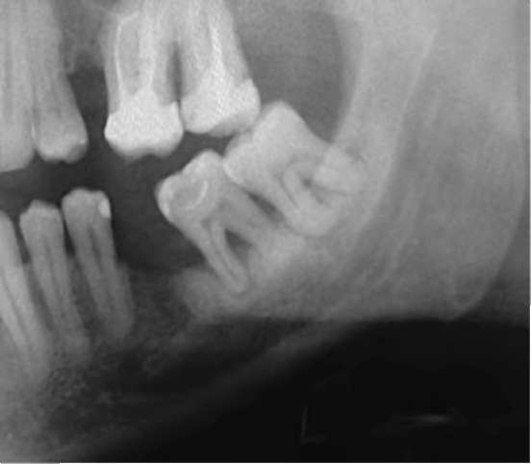

На рентгенограмме нижней челюсти в боковой проекции обращают внимание на положение нижнего зуба мудрости, состояние его периодонта и окружающей кости, отношение его к ветви и каналу нижней челюсти (рис. 14-17).

image

Рис. 14-17. Рентгенологическая картина ретенции зуба мудрости